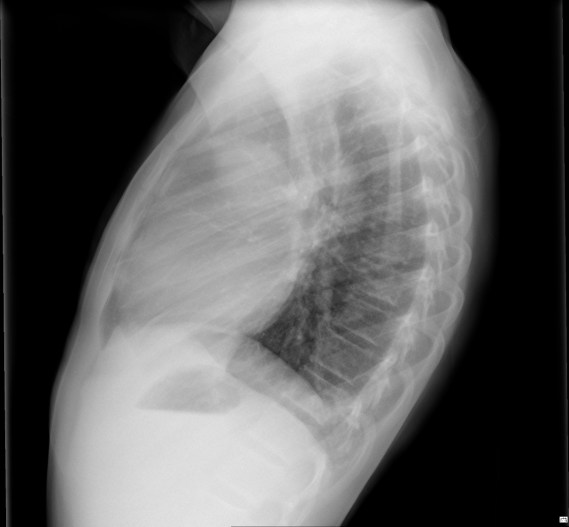

CASO: Febrícula y tos de 4 días de evolución.

Hallazgos:

- En la placa PA se observa una asimetría en los hilios pulmonares, el hilio izquierdo tiene una densidad aumentada.

- Tras examinar la placa lateral se observa un aumento de densidad en la columna que puede ser compatible con una condensación, es el signo de la desnificación vertebral.

SIGNO DE LA DENSIFICACIÓN VERTEBRAL: En la radiografía lateral normal, la densidad de la columna torácica tiende a disminuir desde la parte superior hasta el diafragma; la alteración de ese patrón por la presencia de una densidad superpuesta a la columna, indica la existencia de una consolidación pulmonar. Este signo adquiere especial valor cuando en la proyección posteroanterior la consolidación está oculta en el espacio retrocardíaco o en la base pulmonar.